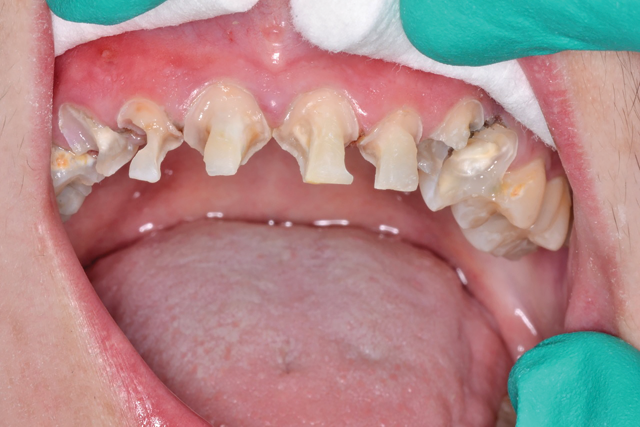

Using 3.5x loupes, caries detecting solution and slow speed excavation, I removed massive amounts of decay throughout the arch (Fig. 3). There were pulpal exposures in teeth # 6, 10 and 11, and I immediately performed same-day root canals.

Fig. 3 Fig. 4